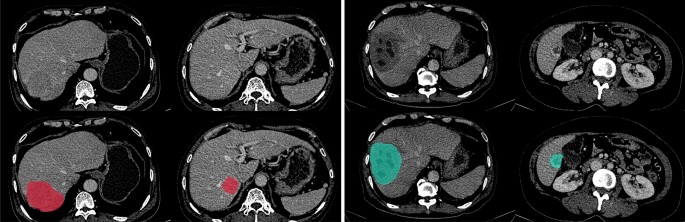

Examples of CT venous slices (top row) and the hepatic lesion annotation overlaid (bottom row) in out dataset. HCC tumors (red) are in the first two CT slices, and non-HCC lesions (cyan) are in the last two CT slices. Best view in color.

In the annotating step, the radiologists then manually annotated the 3D region of the lesion using the free and open-source 3D Slicer imaging platform35. Based on the screening information, the radiologists used the CT phase specified in the screening step that provided the clearest depiction of the lesions to annotate all FLLs, except the one with a diameter smaller than 5 mm. Two radiologists independently annotated each lesion to guarantee the accurate mask of the FLLs. The annotation was accepted if two independent radiologists’ lesion masks reached a consensus with a Dice score greater than 0.8. Otherwise, the radiologists must discuss to confirm the annotated masks of lesions. Each lesion’s ground-truth mask was considered the intersection of the accepted annotations. Figure 1 visualizes the intersect annotated masks of the HCC and non-HCC lesions overlaid on the venous phase series. After the labeling process, we obtained 391 lesion masks from 253 patients, with 158 HCC tumors from 129 patients and 233 non-HCC lesions from 145 patients. The mean annotation consensus between radiologists in terms of Dice score was 0.92. A summary of the dataset is presented in Table 1. It is worth noting that rigid registration was performed to align the phases of each case study together. In particular, the arterial and delayed phases were automatically registered into the venous phase through our developed registration algorithm based on the iterative closest point technique.